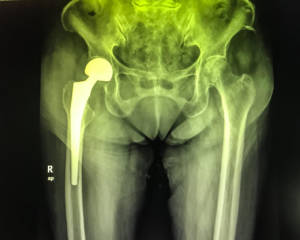

I distretti corporei maggiormente coinvolti sono: anche, colonna vertebrale, polsi, spalle e femore. Da notare che una frattura al femore, può condurre il soggetto colpito a una condizione di disabilità fisica.

La frattura al femore è il caso più drammatico di osteoporosi severa. Essa è indice del fatto che l’osteoporosi ha alterato in maniera significativa la resistenza del nostro tessuto scheletrico aumentando la fragilità ossea portando a questo evento traumatico.

Le sue conseguenze sono una diminuzione della densità minerale ossea e un aumento della fragilità e debolezza dell’apparato scheletrico con predisposizione alla comparsa di fratture al collo del femore, al femore, ai corpi vertebrali, all’avambraccio e alla parte prossimale vicino alla spalla per quanto concerne la frattura dell’omero.

Queste fratture spesso richiedono un intervento chirurgico per la loro riparazione.

Spesso chi ha avuto fratture al femore presenta fratture vertebrali senza saperlo. I Pazienti che hanno subito una frattura al collo del femore, presentano in oltre il 50% dei casi, anche delle fratture vertebrali.

Una frattura al femore può anche ridurre il soggetto colpito in condizioni di disabilità fisica nel 20% – 30% dei casi.

- all’estremità prossimale del femore, in zona inguinale;

- alle anche, intorno al bacino.

Attenzione: perché il femore può subire ulteriori fratture dopo la prima: nei successivi 5 anni dalla prima frattura le probabilità di subirne una nuova salgono al 20%. E le possibilità che venga colpito da frattura il femore della gamba opposta salgono al 50%. Spesso la frattura al femore può richiedere una lunga degenza.

Le persone che hanno subito una frattura al femore prossimale presentano un tasso di mortalità del 15% – 30% entro un anno dalla frattura.

Il femore è l’osso più lungo e resistente dello scheletro. È situato fra l’anca e il ginocchio e vi si inseriscono molti muscoli fondamentali per il movimento della gamba.

La sua resistenza può però ridursi con l’invecchiamento e può fratturarsi a livello del collo per minimi traumi o anche in loro assenza.

- in caso di intervento al femore, dovremo utilizzare un bastone d’appoggio per camminare, adeguandolo alla statura e portandolo dal lato della gamba non fratturata.

- Ai soggetti osteoporotici portatori di protesi d’anca.